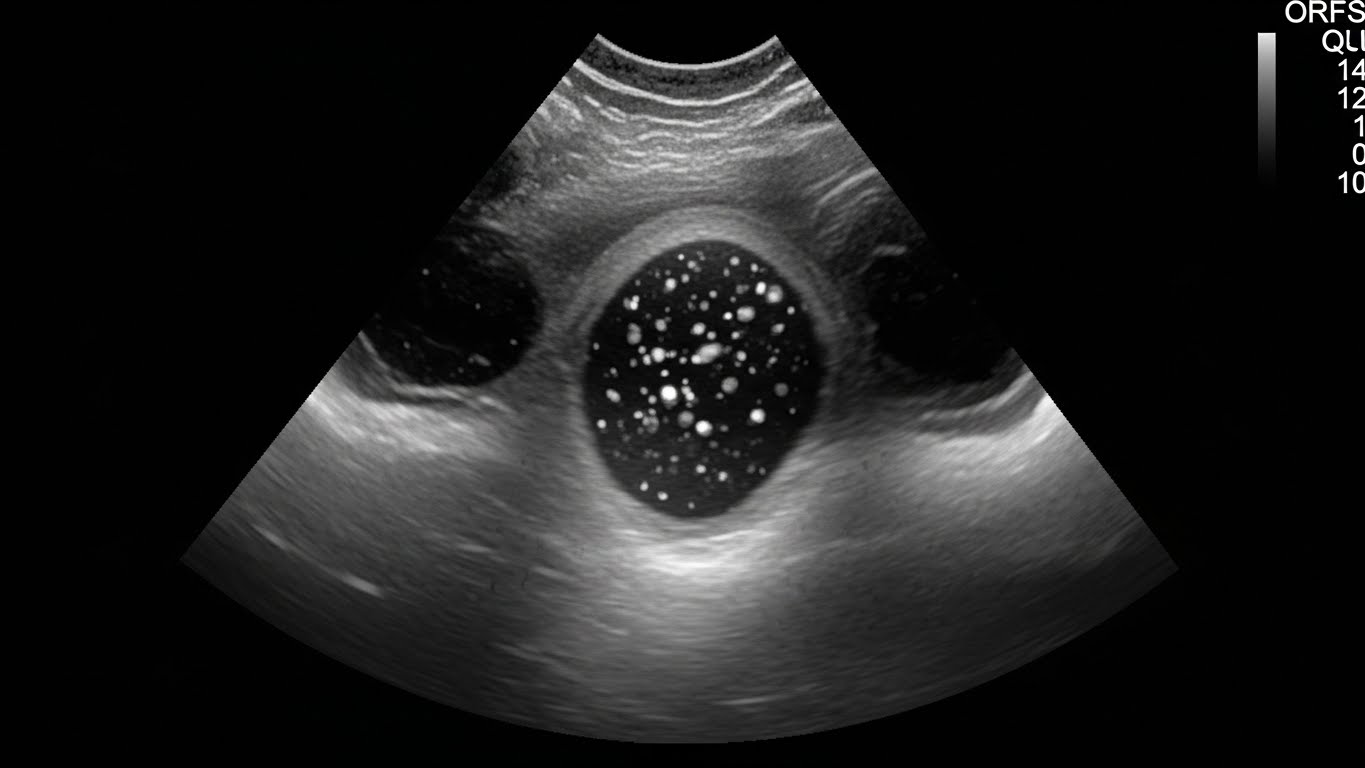

- 갑상선 초음파 검사

- 갑상선 결절, 크기, 염증 여부 확인